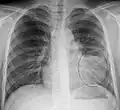

| A chest X-ray showing a very prominent wedge-shape bacterial pneumonia in the right lung | |

Normal AP CXR